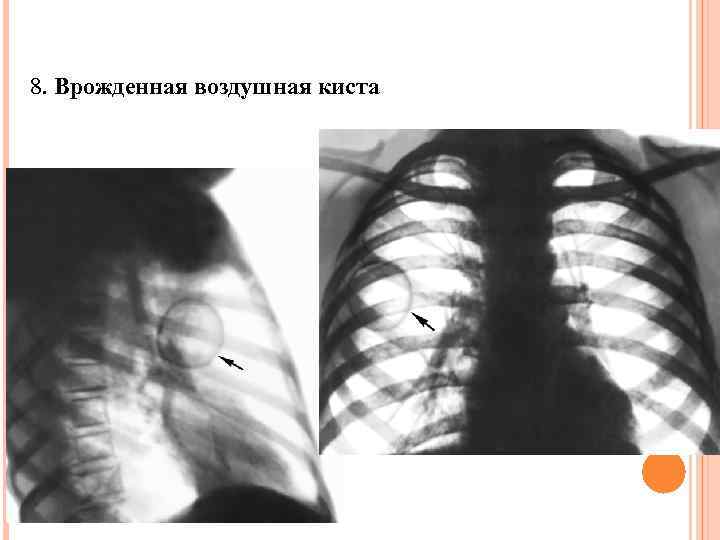

8. Врожденная воздушная киста

8. Врожденная воздушная киста